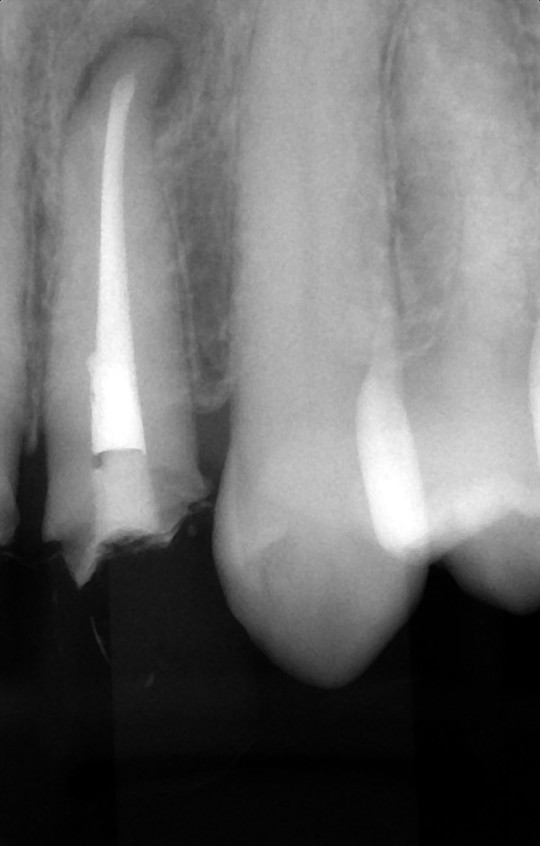

根の先の骨の感染が治らない状態

歯根端切除術・MTA充填直後

術後1年2か月

骨は順調に回復中

根管治療でなかなか根尖病巣が治癒しない、再発を繰り返す、など難治性の根管治療と呼ばれる状態になってしまうことがあります。その場合に、局所麻酔下で外科的に根尖病巣にアプローチして、治す方法があります。

『歯根端切除術』は歯ぐきを剥離して、感染している根尖病巣と根の先端を切除したうえで、根の切断面の根管からMTAという材料を充填する方法です。感染部分を直接きれいにすることができるのに加えて、MTA(アルカリ性の水硬性セメント)の作用で、持続的な殺菌と骨を作る細胞への刺激が期待できます。上手く経過すると、一回の外科処置で、完全に根の先の骨が再生します。

『意図的再植術』は一度歯を抜歯し、感染している根尖病巣と根の先端を清掃し、MTAを充填したうえで、再び歯をもとの位置に戻して固定する方法です。行っていることの本質は『歯根端切除術』と同じです。

二つの方法は状況に応じて使い分けます。まずは徹底した非外科の根管治療を行うことが前提ですが、どうしてもうまくいかない場合に、抜歯の前にこういった方法をとることも可能です。